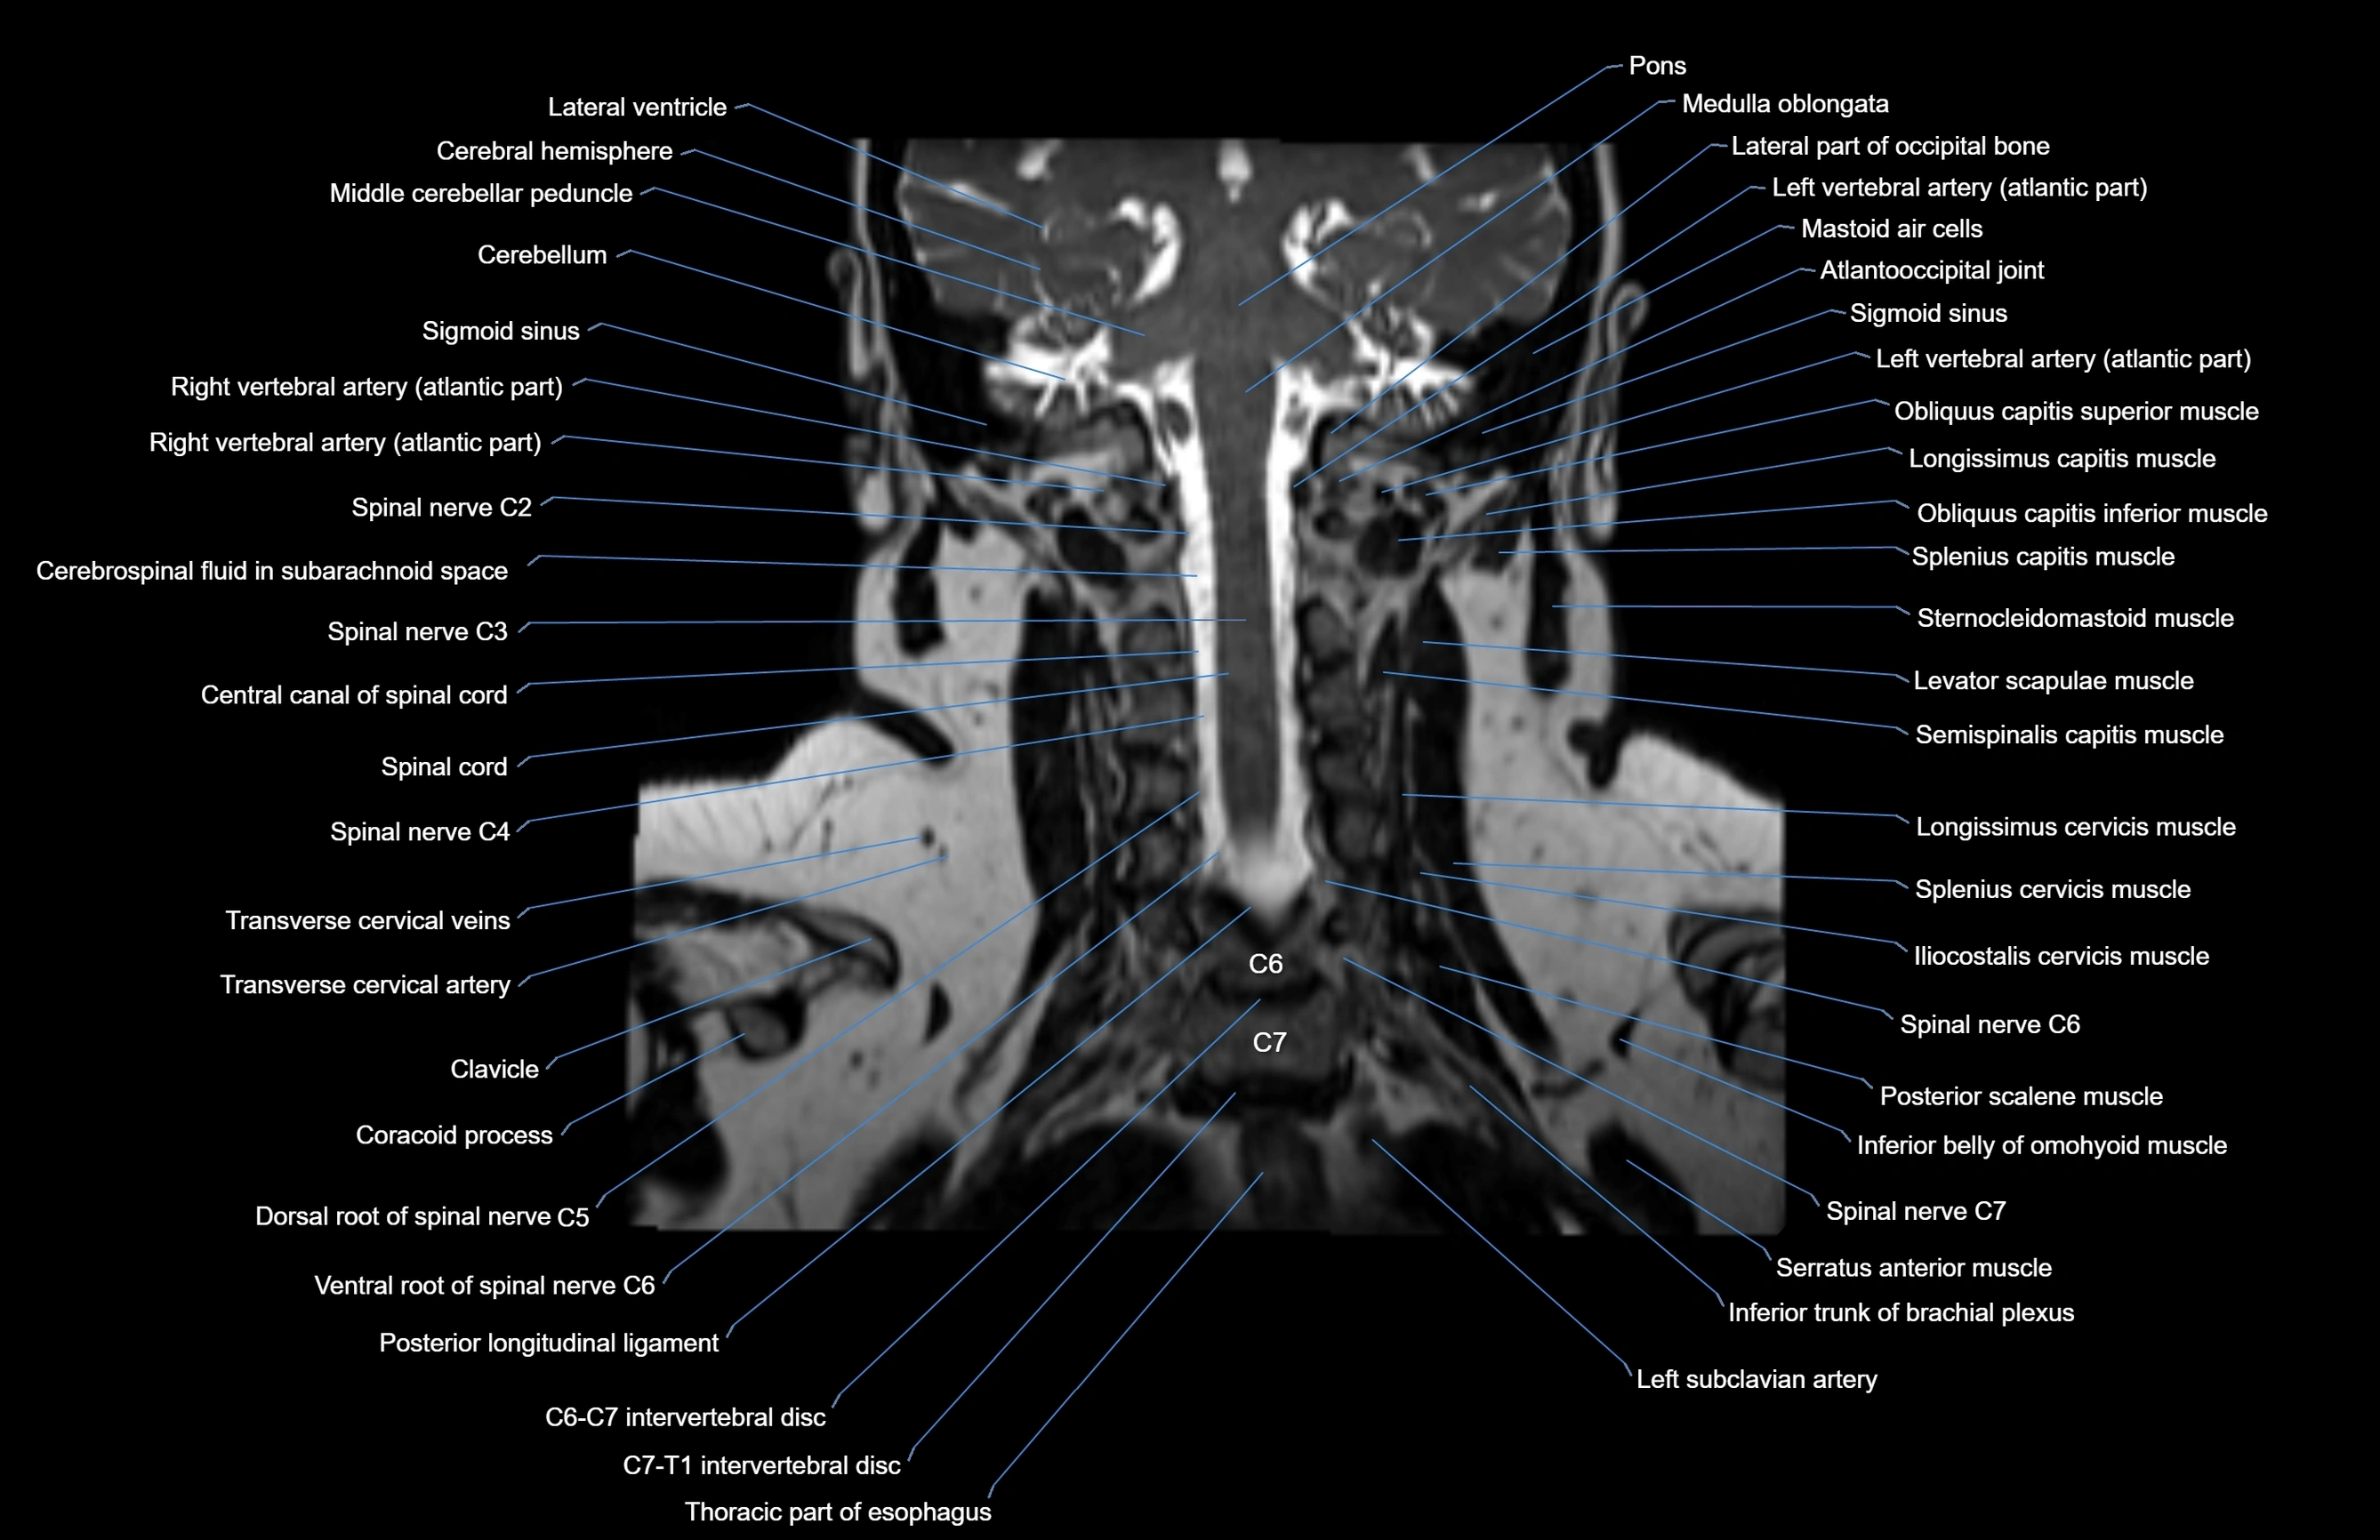

MRI images